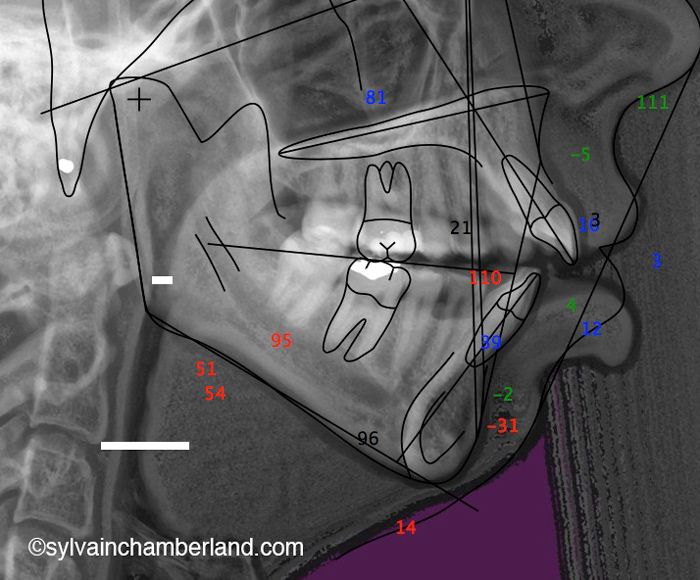

Sur la radiographie de gauche, la plus grande barre horizontale représente la 2e vertèbre cervicale. Normalement, l’angle goniaque est situé à cette hauteur. La résorption des condyles a causé un raccourcissement de la branche montante de sorte que l’angle goniaque se trouve à hauteur de la 1re vertèbre cervicale. La petite barre horizontale indique la largeur du tractus oropharyngé. il faut avoir normalement 10 à 15 mm. Dans ce cas, il y a à peine 5 mm de largeur.

Remarquez la distance entre les racines des dents postérieures supérieures et le palais comparativement au cas suivant où cette distance est augmentée.

Dans ce cas-ci la béance s’explique par un excès vertical du maxillaire. Observez, sur la radiographie céphalométrique de gauche, la grande distance entre les racines des dents postérieures supérieures et le palais. C’est l’indication d’un excès vertical. La longueur de la branche montante est normale et l’angle goniaque est à la hauteur de la 2e vertèbre cervicale.

Vous pouvez aussi comparé avec le tracé céphalométrique du cas précédent avec résorption des condyles. Il est facile de constater que l’angle goniaque est au niveau de C2 et que l’espace oropharyngé est plus large.